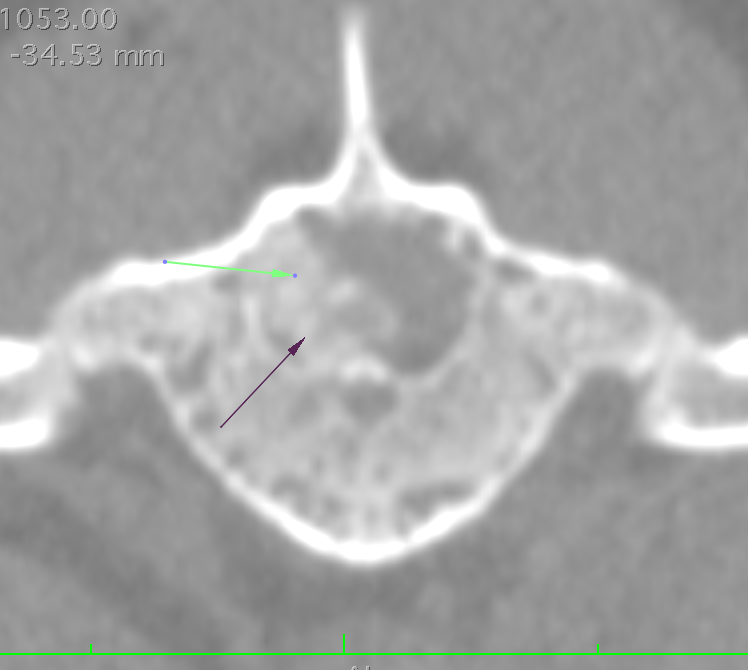

Sagittal (top), axial (bottom) and coronal (left) images of an extruded disc from a dog with IVDD. Arrows denote extruded disc material in axial and coronal images. The red arrow in the top image shows a heavily mineralized disc that has not yet ruptured. The green arrow shows the diseased disc space.